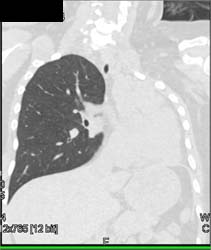

Lung Cancer